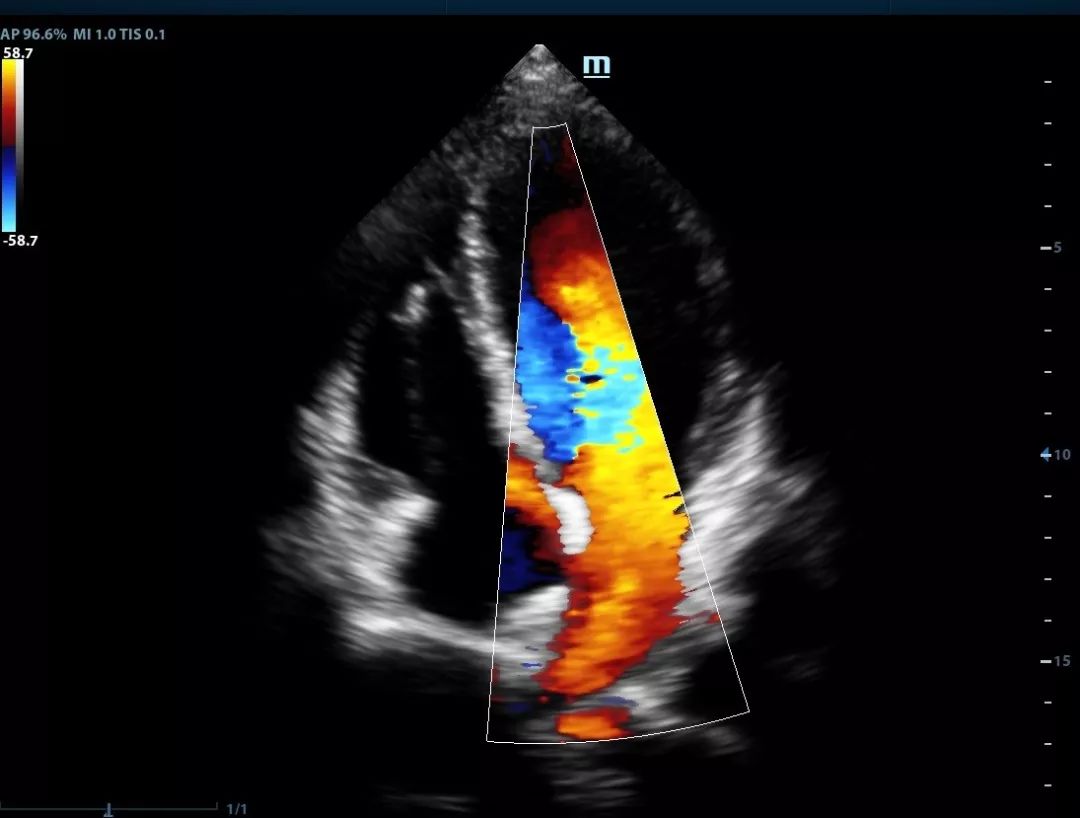

Single crystal transducers with 3T technology

Mindray's unique single crystal transducers with 3T technology

(Triple-matching layers, Total-cut design and Thermal control) provide a wider bandwidth to simultaneously offer better penetration and higher resolution. Integrating the brand-new single crystal volume, convex and phased array transducers with the system, X-Insight makes an optimum scanning solution in OB/GYN, ABD, Cardiology, and more.

Gallbladder polyp

Fetal heart sclerosis

Four chamber view